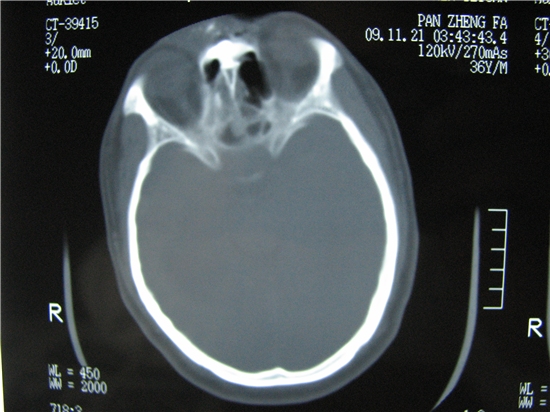

标题: CT23231:男 32岁 车祸伤,鼻腔内出血明显。 [打印本页]

标题: CT23231:男 32岁 车祸伤,鼻腔内出血明显。

额窦里是什么,骨窗怎么不清晰,是不窗宽窗位的事。

软组织及额窦内异物

额窦内及额部软组织内可见多发游离类骨质密度影,考虑额骨骨折可能。

鼻骨层面较少,无法判断鼻骨。

建议薄扫一下。

左侧额骨、鼻骨骨折,头面部软组织肿胀。

左侧额骨、鼻骨骨折,额窦内的应该是游离骨块